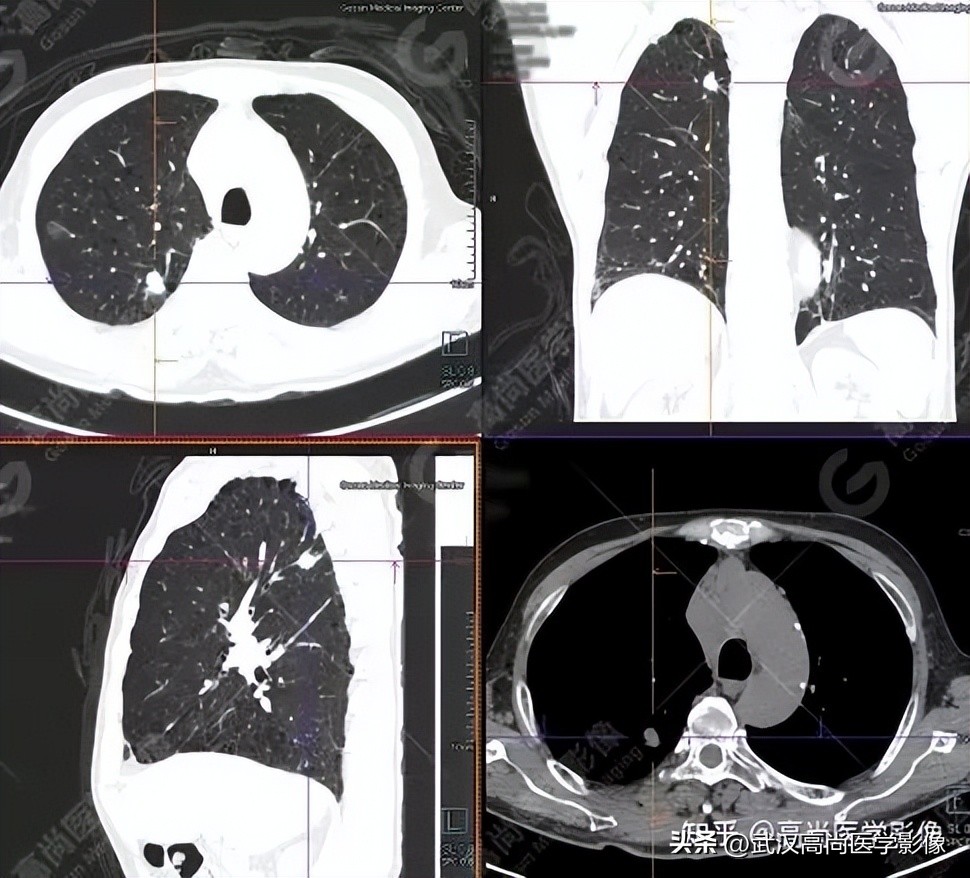

右肺上叶后段一实性结节,大小约1.4cm×1.0cm×1.2cm,边缘分叶征、棘状突起,邻近胸膜稍牵拉,FDG高摄取,SUVmax6.6。

高危结节